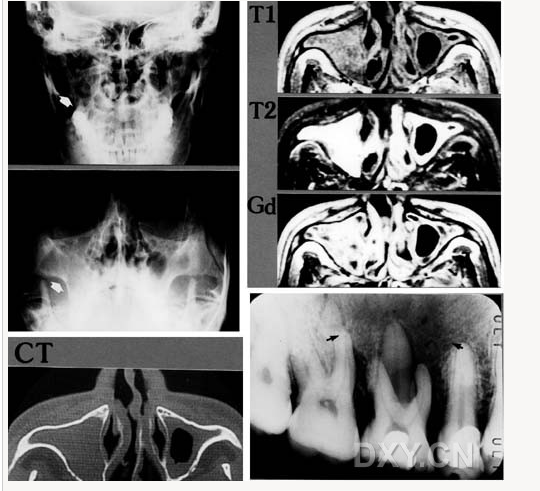

骨肉瘤

涎石病

舍格倫綜合征